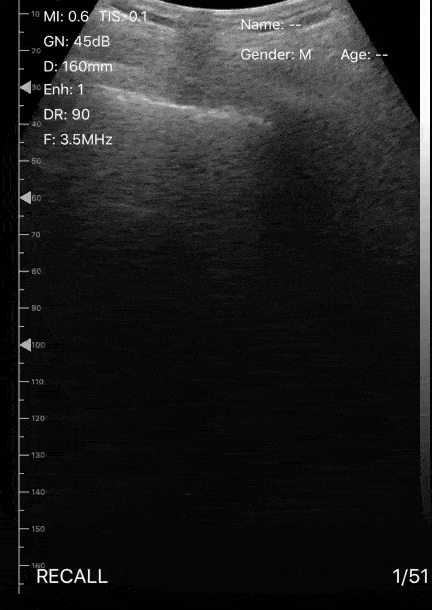

This clip demonstrates the presence of focal B lines with pleural irregularity. The patient presented to the ED with cough and O2 saturation varying between 87-89%, with no respiratory distress or significant past medical history. One of the patient’s family members was currently under investigation for COVID-19. The entire lungs were examined and the image above is the PLAPS view. Later the patient had a CT done which showed ground-glass opacity peripherally compatible with areas scanned on the POCUS exam. Pearl: POCUS may be an excellent tool for the triage of these patients. Image Courtesy of Dr. Victor Bang (@vmjbang) Co-Founder of Pocus Jedi